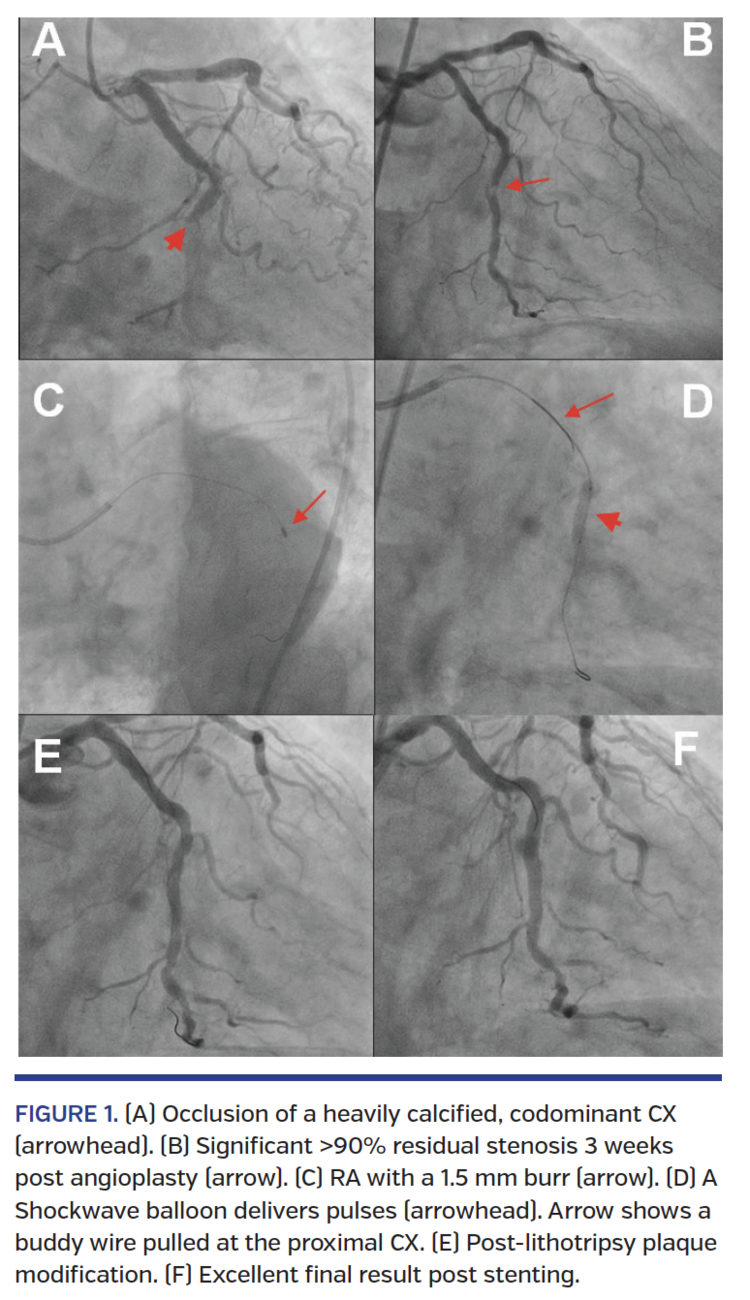

A 66-year-old man with end-stage renal disease was admitted with inferolateral STEMI due to occlusion of a heavily calcified circumflex (CX) artery (Figure 1A; Video 1). Primary angioplasty was performed and flow was restored after dilations with a 1.5 mm balloon. A 2.0 mm balloon was advanced over the lesion only after using a buddy wire and a guide-catheter extension, but could not be expanded adequately. We were unable to advance a 2.5 mm non-compliant balloon despite implementing the above highly supportive maneuvers. The procedure was completed at this stage, with TIMI 3 flow across the CX (Video 2).

Three weeks later, the patient was brought back to the cath lab. A significant >90% residual stenosis was present in the calcified CX (Figure 1B; Video 3). Rotational atherectomy (RA) was performed using a 1.5 mm burr at 180,000 rpm (Figure 1C; Video 4). However, the lesion was undilatable using a 3.0 non-compliant balloon at high pressure. Therefore, we employed intracoronary lithotripsy (Shockwave Medical) for additional modification of the calcified plaque. Using a 3.5 x 12 mm Shockwave balloon, we delivered 3 runs of 10 pulses with excellent expansion of the balloon at low pressure (4-6 atm) (Figure 1D; Video 5). Post-lithotripsy angiogram showed a significant modification of the calcified lesion (Figure 1E; Video 6). We then implanted two 3.5 mm zotarolimus-eluting stents followed by postdilation with a 4.0 mm non-compliant balloon, with excellent angiographic result (Figure 1F; Video 7).